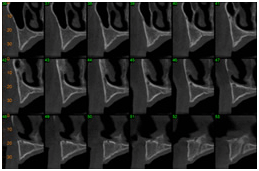

As imagens visualizadas abaixo representam os cortes tomográficos transversais oblíquos efetuados na imagem guia. Nesse caso foram realizados cortes tomográficos com espessura de 1mm e distância entre cada corte também de 1mm. Essa seleção é feita pelo operador do tomógrafo e permite escolher a distância e a espessura dos cortes que podem ser de 1 ou 2mm.

TC cortes transversais obliquos TC cortes transversais obliquos

TC cortes transversais obliquos